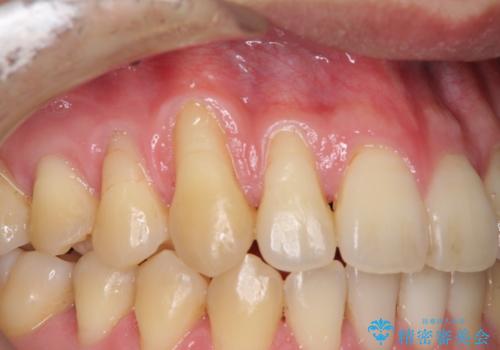

八重歯の歯根が見えている点も気になっているので、矯正歯科治療後に歯肉移植による根面被覆を行うこととしました。

矯正治療により元々気になっていた八重歯と、反対咬合が改善された歯の2本に対して根面被覆を行い、審美面の改善も達成しました。